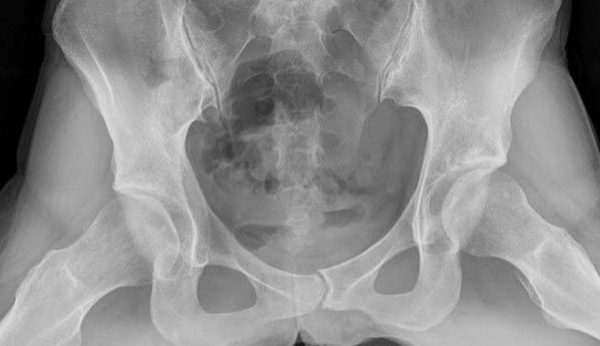

El masaje perineal es una técnica de terapia manual que consiste en un conjunto de maniobras, presiones y estiramientos que ayudan a los músculos del suelo pélvico y a la entrada de la vagina a estar más elásticos; con el fin de prepararlos para el momento del parto y evitar los tan indeseados traumas perineales.

Como se ha dicho anteriormente, el masaje perineal ayuda a elastificar y preparar el suelo pélvico; de tal forma que el día del parto, le sea más sencillo abrirse para que salga el bebé.

Vivir tu embarazo de forma consciente y conocer tu pelvis al máximo antes del parto, son factores muy importantes a la hora de afrontar la dilatación, el expulsivo y la recuperación post-parto.